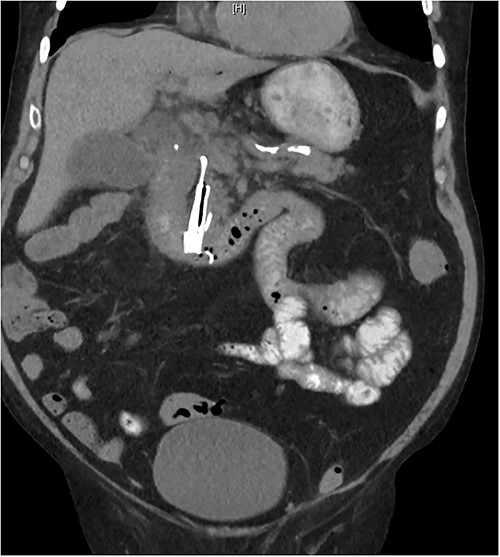

On presentation, there was no signs of shock, with a blood pressure of 152/70, heart rate of 88 and oxygen saturations of 94% on room air. A temperature of 38.1°C, however, was noted and physical examination revealing a distended abdomen with right lower quadrant tenderness. He had no peritonism and digital rectal examination showed an empty rectum. Biochemical investigations showed a white blood cell count of 20.00 × 109/L, C-reactive protein level of 126 mg/L, eGFR of 32 ml/min/1.73 m2, creatinine of 153 umol/L; he had normal liver function tests, coagulation profile and electrolytes. A computed tomography (CT) abdomen and pelvis with intravenous contrast revealed a distally migrated metallic biliary stent located in the terminal ileum with mildly dilated loops of distal small bowel indicating early or incomplete small bowel obstruction (Fig. 2).

Abdominal CT showing migrated biliary stent in sagittal (A), coronal (B) and transverse (C) views.